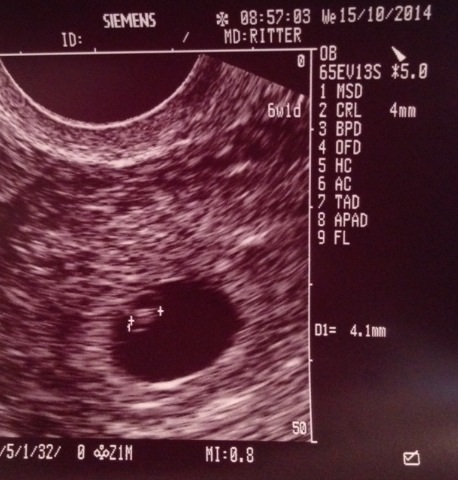

• My OB tracked me at 6w1d today. Here is today's US and the next one is at 16 weeks